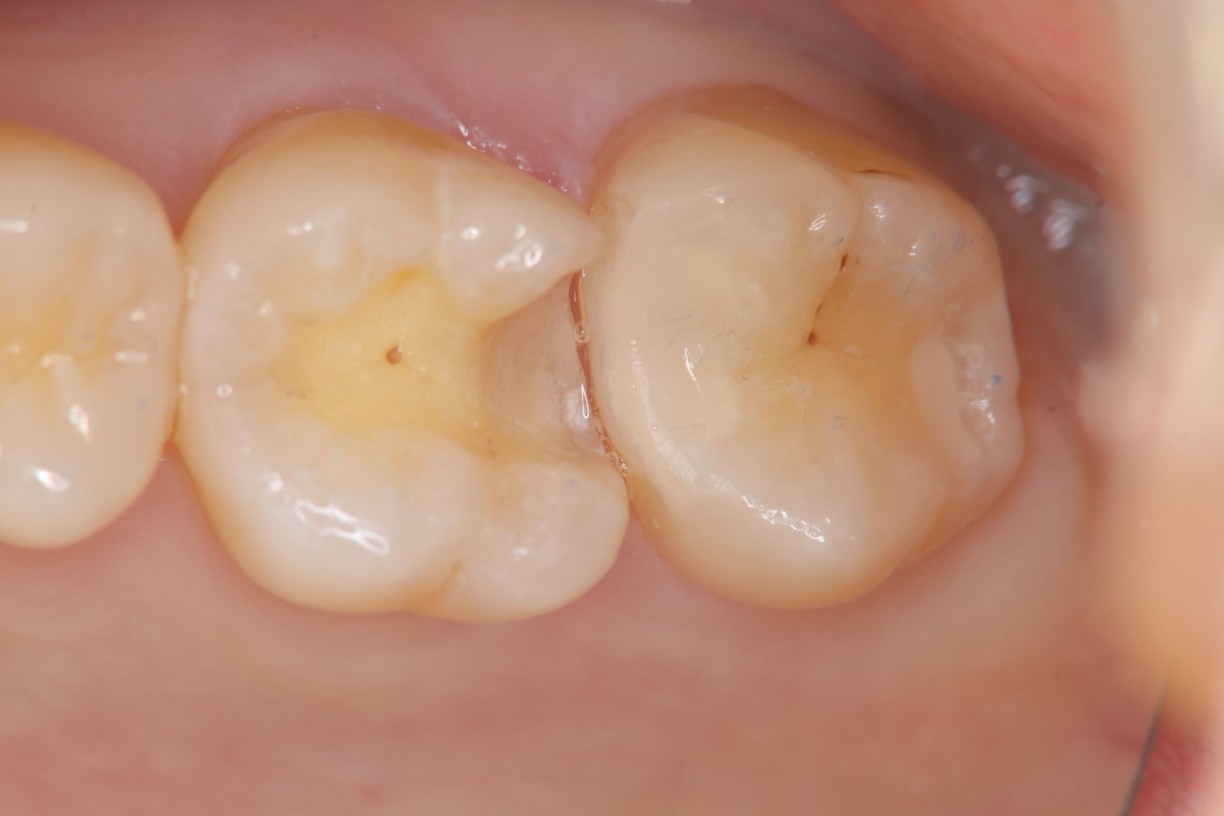

瓷塊製備